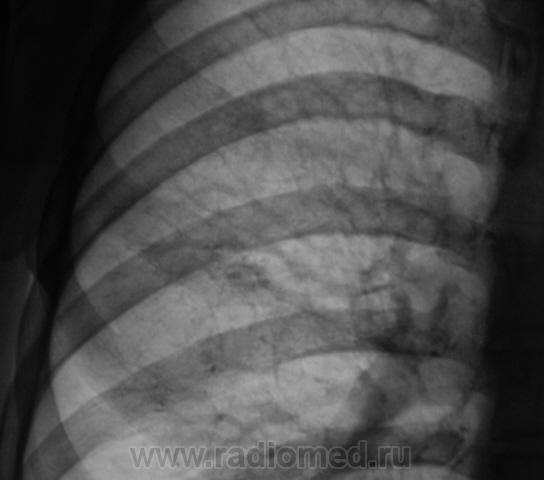

2 срез

В s 1 -2 и глубоких отделах s6судя по срезам очаги,справа с включениями кальция,на фоне фоброзно измененного легочного рисунка

Скорее диссеминирмванный так как пораженно более 2-х сегментов.